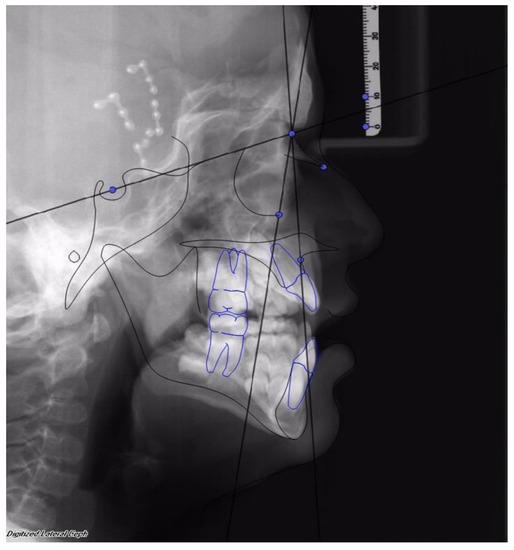

Facial advancement was satisfying for every patient, only the advancement of patient 1 should have been greater in order to reach the appropriate projection. Clinical results were anyway satisfying, so no further surgical procedure was undertaken. (See Figure 2 and Figure 3).

Figure 2. First patient, female, 6 years old, affected by Crouzon’s Syndrome. Osteodistraction (OD) was removed after 40 days before the established time of osteodistraction for fractures of bone support caused by accidental trauma. Osteodistraction was finished with an advancement of 23 mm. The advancement was interrupted before the normalization of the SNA angle to stop bone advancement. After removal of the OD device, the SNA was 75° and the SNOr was 63°.

Figure 3. The same patient after 1 year from the end of treatment with MAC. SNA was 76° and SNOr was 63°.